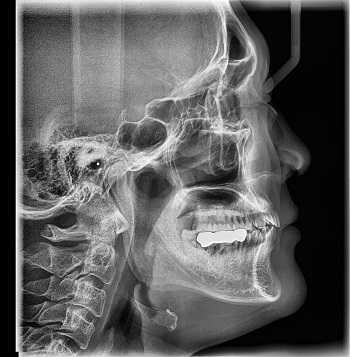

- Рентгенография. На этапе первичной диагностики больных с подозрением на фибросаркому направляют на рентгенологическое исследование. По данным рентгенографии определяется узел овоидной формы с однородной структурой и нечеткими границами. В области узла могут выявляться участки обызвествления, при распространенных процессах отмечается узурация кости.

Наиболее старый и привычный метод визуализации человеческого тела. Применяют рентген повсеместно, от хирургии до стоматологии. Метод прост и понятен: человека облучают особыми лучами, которые легко проходят сквозь мягкие ткани и задерживаются в твёрдых. Благодаря этому принципу, на фотоплёнку или датчик, расположенные на противоположной от источника лучей стороне, передаётся изображение, а в распоряжение врача попадает рентгенография или рентгеноскопия.

Рентгенография

Принцип работы рентгеновского аппарата заключается в том, что рентгеновские лучи, проходя через разноплотную среду исследуемой области, по-разному ослабляются: более плотная костная ткань в значительной степени поглощает рентгеновское излучение, менее плотная подкожно-жировая клетчатка ослабляет его в небольшой степени, а воздух, содержащийся в околоносовых пазухах или легких, не задерживает совсем. Эти неравномерно ослабленные пучки рентгеновских лучей, попадая на светочувствительный слой пленки, формируют рентгенограмму — изображение, которое отображает все структуры исследуемой области, наслаивая их друг на друга. При этом получаемый снимок позволяет определить форму, размеры и строение исследуемой области, выявить или заподозрить структурные нарушения, а исследование в двух или нескольких проекциях позволяет определить локализацию выявленных изменений. Чаще всего рентгенография используется для исследования костей, легких, почек, кишечника.